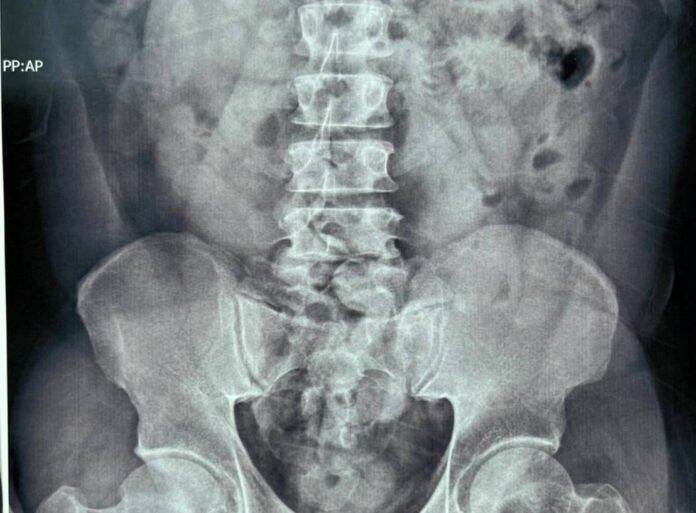

เจ้าหน้าที่กรมศุลกากรและเจ้าหน้าที่ชุดปฏิบัติการ AITF จึงจัดชุดสังเกตการณ์ด้านนอกโรงแรม จนในวันที่ 6 มีนาคม 2565 เวลา 10.00 น. ผู้โดยสารคนดังกล่าวได้ออกจากโรงแรมกักตัว เจ้าหน้าที่ได้เข้าตรวจค้นและนำตัวไปทำการเอกซเรย์ที่โรงพยาบาล ผลเอกซเรย์บ่งชี้ว่า ผู้ต้องหามีสิ่งแปลกปลอมในช่องท้อง จึงได้นำตัวผู้ต้องหาไปทำการขับถ่ายที่สำนักงานสุวรรณภูมิ เสร็จสิ้นเมื่อวันที่ 8 มีนาคม 2565 จากการตรวจสอบพบวัตถุแปลกปลอมเป็นยาเสพติดประเภทโคเคน จำนวน 54 ก้อน น้ำหนักรวม 1,080 กรัม มูลค่าประมาณ 3,240,000 บาท จึงได้แจ้งข้อหาให้ชายคนดังกล่าวทราบว่า การกระทำดังกล่าวเป็นความผิดฐานนำเข้ายาเสพติดให้โทษประเภท 2 และครอบครองยาเสพติดให้โทษประเภท 2 โดยไม่ได้รับอนุญาต ตามประมวลกฎหมายยาเสพติด และเป็นความผิดตามมาตรา 244 แห่งพระราชบัญญัติศุลกากร พ.ศ. 2560 จากนั้นนำผู้ต้องหาพร้อมของกลางส่งพนักงานสอบสวนดำเนินคดีต่อไป